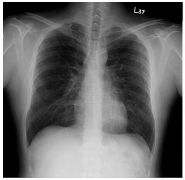

4.

10. CC: 咳嗽 1 周,有痰